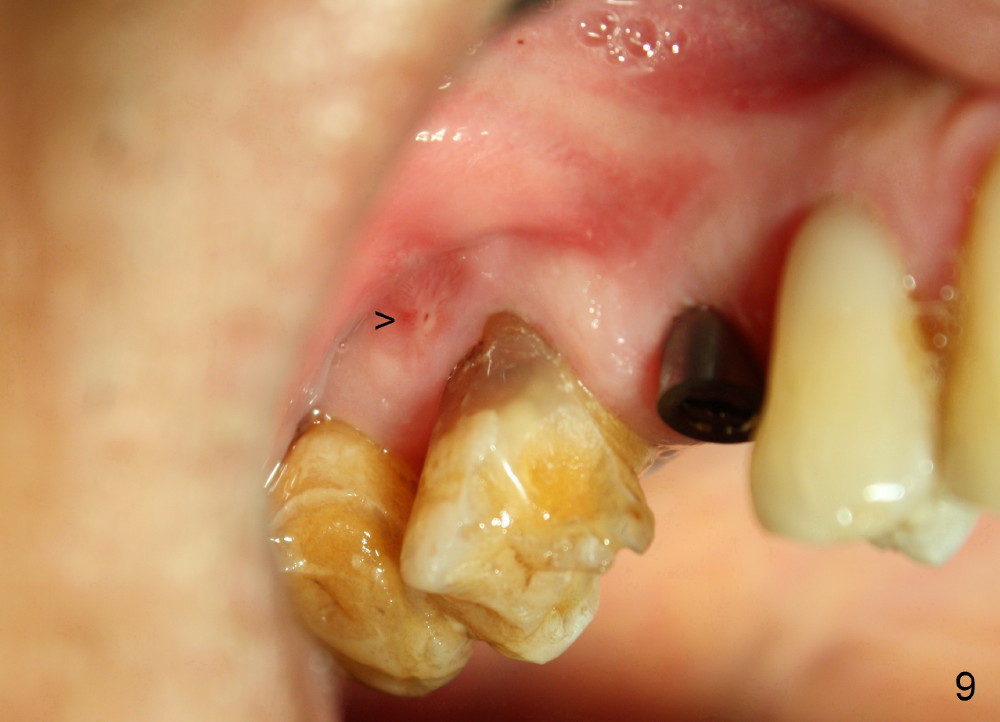

A 72-year-old man is a bruxer with #3 cusp fracture with chronic periapical radiolucency (Fig.1 *) and #4 acute crack.  It appears reasonable to take care of emergency (#4 extraction and immediate implant (Fig.3-7: 4.5x20 mm, 45 Ncm)) followed by root canal therapy or extraction for #3.  Eight (Fig.8) and 14 (Fig.9-11) days postop, the patient is doing fine and the wound heals normally.  But he does not agree any treatment for #3, since it is asymptomatic in spite of a fistula associated with the tooth (Fig.8,9 >).  Three months postop, the patient is still asymptomatic and is ready for #4 restoration since the tooth #28 cracks.  Follow-up PA shows the persistent distal gap (Fig.12 >, as compared to Fig.4), accompanied with crestal bone resorption (*).  Clinically the implant has mild mobility and light tenderness. The patient still refuses #3 treatment. It appears that the implant has failed to osteointegrate.  In brief, do not place an immediate implant next to active infection.